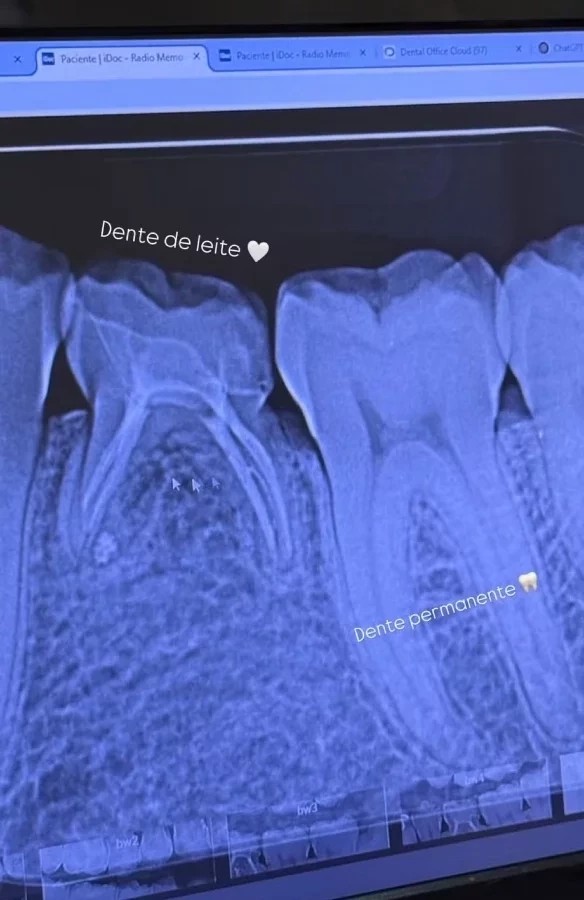

"Eu tenho uma coisa muito específica que a gente conseguiu ver na radiografia, gente, que é um dente de leite. Até hoje. Enquanto o siso nasce agora, com 24 anos, eu sigo com 24 anos tendo um dente de leite. E ele é tão bonitinho, dá para ver, assim, obviamente, muito diferente do meu dente permanente, mas ele é uma fofura, uma fofura. Está lá, lindinho; não tem um outro dente, por isso que ele não caiu, e a gente segue cuidando justamente para manter uma boca saudável", contou ela.

Radiografia Larissa Manoela. Foto: Instagram